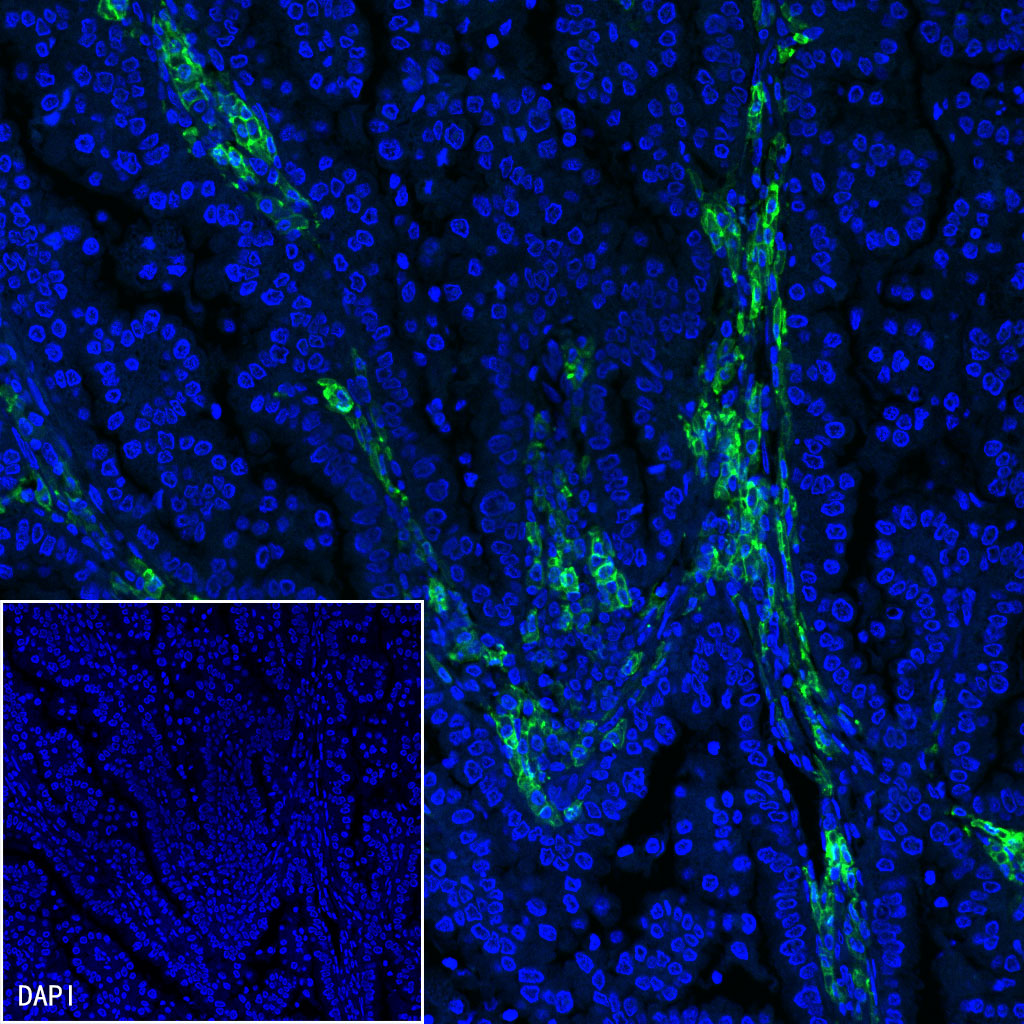

Immunofluorescence

IF shows positive staining in paraffin-embedded human cervical squamous cell carcinoma. Anti-CD38 antibody was used at 1/500 dilution (Green) and incubated overnight at 4°C. Goat polyclonal Antibody to Mouse IgG - H&L (Alexa Fluor® 488) (S0B4017) was used as secondary antibody at 1/500 dilution. Counterstained with DAPI (Blue). Heat mediated antigen retrieval with EDTA buffer pH9.0 was performed before commencing with IF staining protocol.

IF shows positive staining in paraffin-embedded human lung adenocarcinoma. Anti-CD38 antibody was used at 1/500 dilution (Green) and incubated overnight at 4°C. Goat polyclonal Antibody to Mouse IgG - H&L (Alexa Fluor® 488) (S0B4017) was used as secondary antibody at 1/500 dilution. Counterstained with DAPI (Blue). Heat mediated antigen retrieval with EDTA buffer pH9.0 was performed before commencing with IF staining protocol.